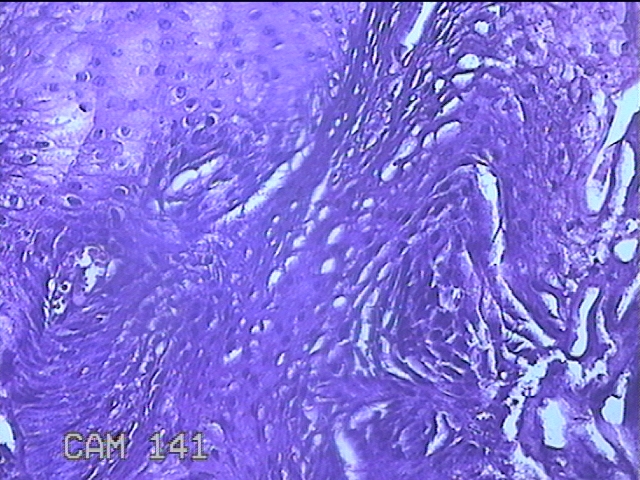

咽部肿物

临床诊断

一般病史

反复咽异物感不适1月。

标本名称

大体所见

灰白粉红色肿物0.8x0.5x0.2cm一个,表面光滑。

图2